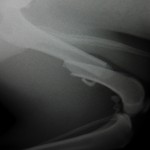

【症例紹介:大腿骨骨折】

大腿骨とは骨盤とすねの骨の間にある太ももの骨です。

落下、事故などでおれてしまいます・・・

1例は2骨片の骨折です。

プレート・スクリューで固定でき、歩行も問題ありません。